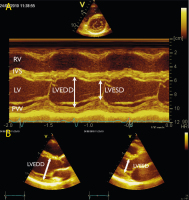

Die standardisierte Echokardiographie: Durchführung, Archivierung und Befunderstellung sowie Evaluierung der systolischen Linksventrikelfunktion // Standardised Echocardiography

Journal für Kardiologie - Austrian Journal of Cardiology 2024; 31 (5-6): 96-103 Volltext (PDF) Summary Abbildungen